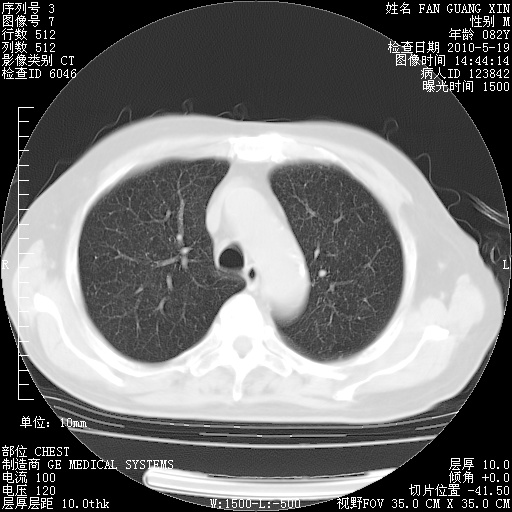

可改为口服强的松40-50mg/d治疗,若病情仍稳定,胸部阴影不再吸收可逐渐减量